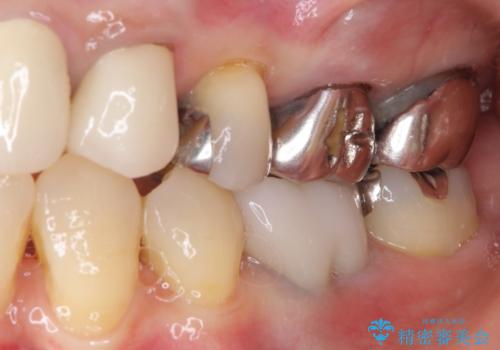

上唇小帯を切除したことで、ブリッジのダミー部分に触れて腫れていた歯肉は健全な状態になりました。

隙間もなくなったことで話す際の空気の漏れや、ものが挟まることもなくなりました。